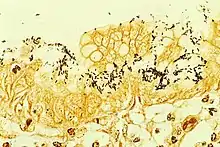

H. pylori can be demonstrated in tissue by Gram stain, Giemsa stain, H&E stain, Warthin-Starry silver stain, acridine orange stain, and phase-contrast microscopy. It is capable of forming biofilms.[26]

An endoscopic biopsy is an invasive means to test for H. pylori infection. Low-level infections can be missed by biopsy, so multiple samples are recommended. The most accurate method for detecting H. pylori infection is with a histological examination from two sites after endoscopic biopsy, combined with either a rapid urease test or microbial culture.[113] Generally, repeating endoscopy is not recommended to confirm H. pylori eradication, unless there are specific indications to repeat the procedure.[111]